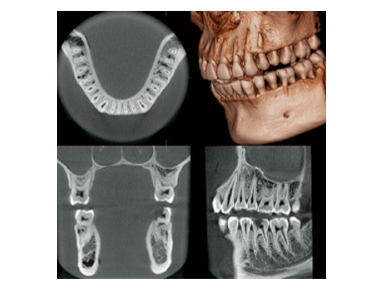

CTはレントゲン撮影の一種で撮影データをコンピュータ処理することで立体的に画像を構築できます(3D画像)。

元来のパノラマやデンタル画像に加えて、3D画像を取り入れることで、口腔内を立体的に観察し、骨の位置や量、病巣の大きさなど診断に重要な要素を把握することができます。

インプラント治療では 顎骨内にドリルで穴を開けます。顎骨内には 下顎には太い神経や血管、上顎には副鼻腔(上顎洞)があり、正確な位置を把握していないと 損傷して麻痺や内出血、感染症を引き起こします。

インプラント治療では、CTで3次元的に位置を把握することが必須であり、最低条件とも言えます。